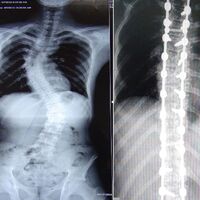

Bir omurga hastalığı olan skolyoz, bel ya da göğüs bölümünde görülmektedir. Omurganın normal eksenden sapması veya dönmesi sebebiyle meydana gelen şekil bozukluğuna denir. Skolyoz konusunda anne babaların çok dikkatli olmaları gerektiğine dikkat çeken Ortopedi ve Travmatoloji Uzmanı Dr. Yunus Atıcı, "Erken tanı için çocukların aileleri tarafından çok sıkı ve düzenli kontrol edilmeleri çok önemlidir. Skolyoz tespit edildiğinde veya en küçük şüphe durumunda bile aileler çocuklarını mutlaka doktora götürmeleri gerekir" dedi.

Sol omuz sağ omuza göre biraz daha aşağıda veya yukarıda ise, çanak kemiğinin biri aşağıda veya yukarıdaysa ya da meme uçlarından biri diğerine göre aşağıda veya yukarıdaysa skolyoz başlangıcı olabileceğini söyleyen Atıcı, “Her iki tarafta bel çukuru birbirine yakın eğimde değilse de skolyoz başlangıcı olabilir. Çocukların sırtına baktığımızda kaburgalarda bir tarafta daha fazla çıkıntı olduğunda, kişiye önden veya arkadan baktığımızda sağa veya sola devrik olması yine skolyoz olabileceğini bize gösterebilir” dedi.

Dr. Atıcı, "Erken dönemde skolyozu tespit ettiğimizde korse kullanarak kontrol altına almamız mümkün olabilir. Geç kalındığında ise hasta ameliyata aday bir duruma gelmiş olabilir. Daha fazla geç kalmanız durumunda ise ameliyat zorlaşır ve çocuğun ameliyat riskleri artabilir. Erken tespit ettiğimizde ise ameliyat süresi 3 saat gibi kısa bir süre iken, eğrilik arttığında 5-6 saat gibi uzun süren ameliyat süreleri ile çocuklarımız karşı karşıya kalabilir" diyerek ailelere uyarılarda bulundu.